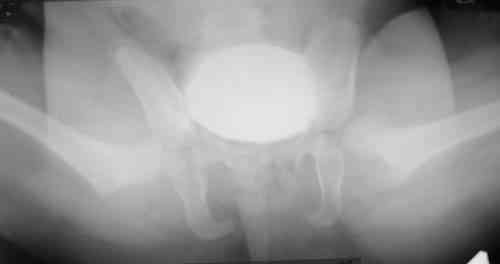

Уважаемые коллеги! Окажите, пожалуйста, консультативную помощь! Девочка, 1 г 9 м ДЗ: врожденная патология головного мозга, врожденная дисплазия, подвывих, приводящая контрактура левого тазобедренного сустава, микроцефалия, миоклонические припадки, грубая задержка психофизического развития, с-м Айкарди?

Жалобы родителей на укорочение левой ноги, невозможность ходить, сидеть. Впервые обратили внимание на укорочение левой нижней конечности 4 месяца назад. Осмотрена по месту жительства в ЦРБ, направлена в ДНИИТО. Ребенок от I беременности, I срочных родов, протекавших с анемией, осложненные преждевременным отхождением вод, вес при рождении 4100. В анамнезе - пупочная грыжа, респираторные заболевания, рахит, тетрапарез, судорожный синдром, сальмонельоз.

Особенности объективного осмотра в настоящее время: Умеренный тетрапарез. Признаки рахита (деформация костей черепа, четки). Дыхание пуэрильное. Тоны сердца ритмичные, шумов нет. Живот мягкий, безболезненный, печень +1,5 см. Склонность к запорам. Местный статус: резкое приведение левого бедра, относительное укорочение левой нижней конечности. Ограничение отведения в тазобедренных суставах, особенно слева. Гипертонус мышц левой нижней конечности. Ограничение сгибания в левом коленном суставе.

Объем движений (левый ТБС): сгибание-разгибание (фиксированное) 65-165; разведение - D 45, S 65. Положение сустава по отношению к линии Розера-Нелатона - D 0,5 см, S 1,5 см. Хронаксиметрия - возбудимость нервных стволов нижних конечностей в норме, двигательная реакция мышц типичная.